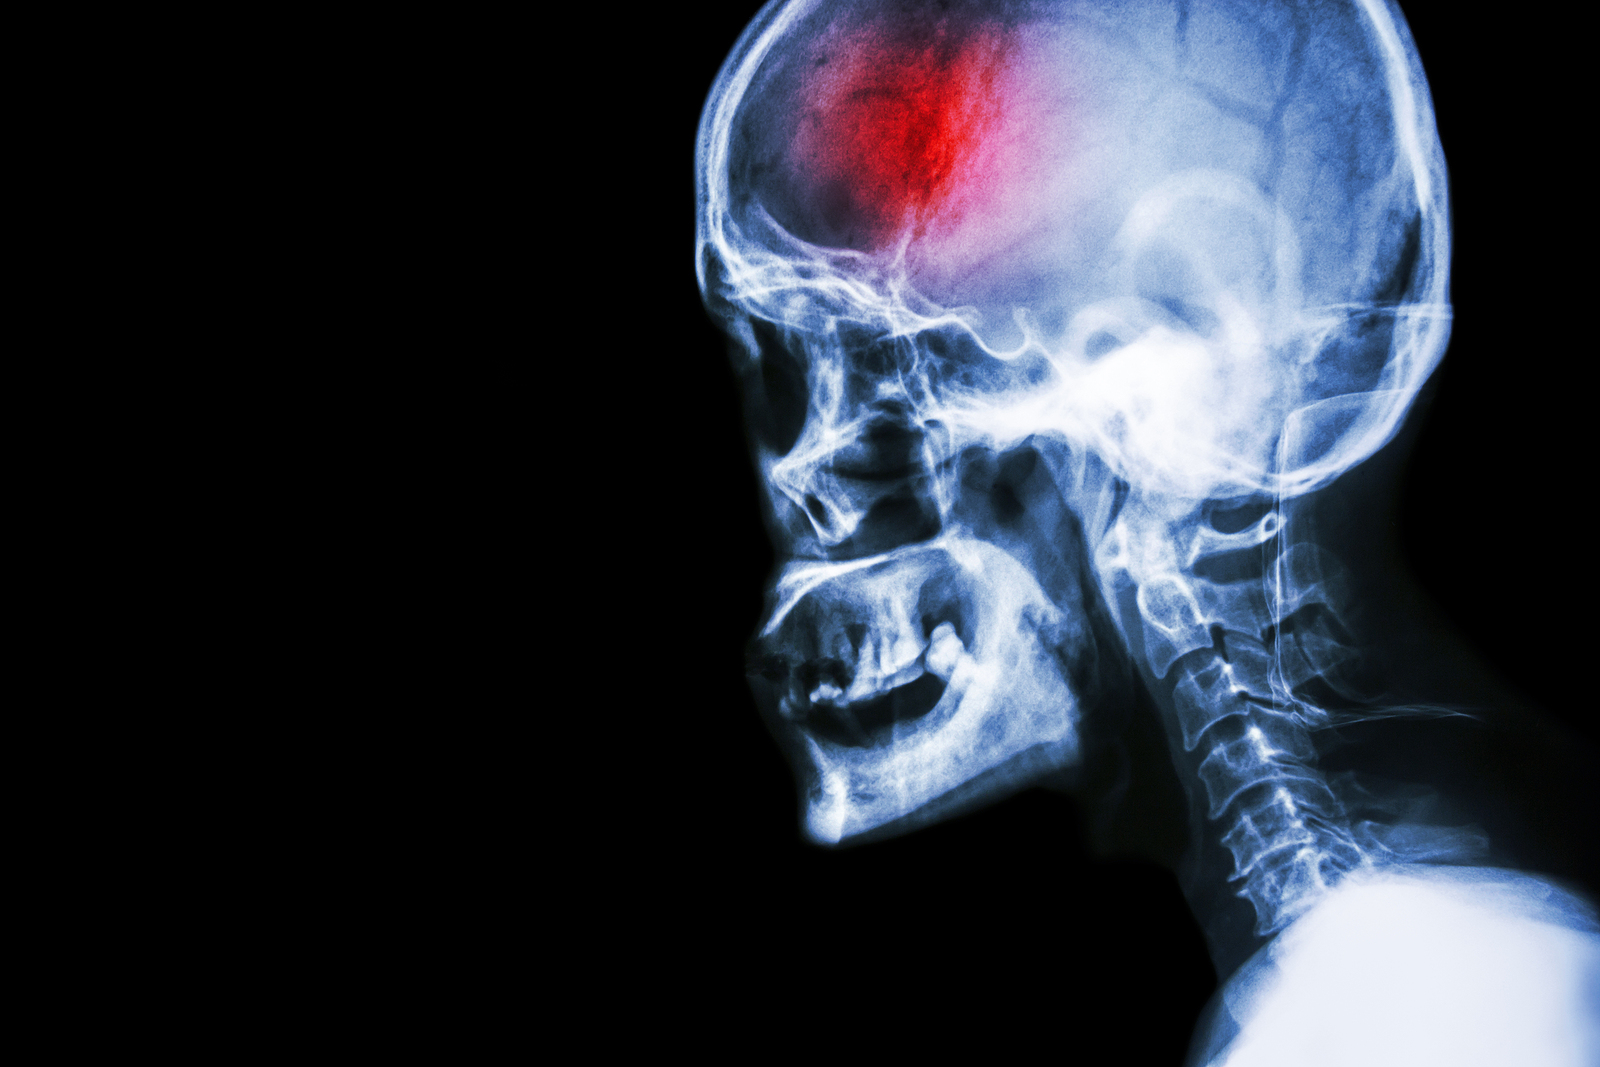

A stroke (previously known as a cerebrovascular accident) when there is a decreased flow of blood to the brain from either a blockage in the blood vessels that supply the brain (ischemic stroke), or a bleed from the blood vessels that supply the brain (hemorrhagic stroke). When the blood flow to the brain is blocked it prevents the brain from getting the needed oxygen and nutrients to function. Without oxygen the brain cells can be permanently damaged or die and the physical and mental functions related to that area of the brain will be affected. A stroke is a medical emergency and rapid treatment is crucial to decreasing the damage caused by a stroke.

- Ischemic stroke: a stroke that is caused by a blockage (clot) that disturbs the blood flow to the brain.

- Hemorrhagic stroke: a stroke that is caused by a bleed that disturbs the blood flow to the brain and puts pressure on the surrounding tissue.

- Transient ischemic attack: often referred to as a “mini-stroke” or TIA, where the blood flow to the brain is temporarily disturbed and as a result causes temporary signs and symptoms of a stroke that resolve quickly .

Computed Tomography (CT) scan and/or Magnetic Resonance Imaging (MRI) scan: These tests are done on your brain and used to locate the exact location of the stroke and to determine if it has been caused by a blockage or a bleed. These tests can also help rule out other conditions that may be causing symptoms, such as an infection or a brain tumour